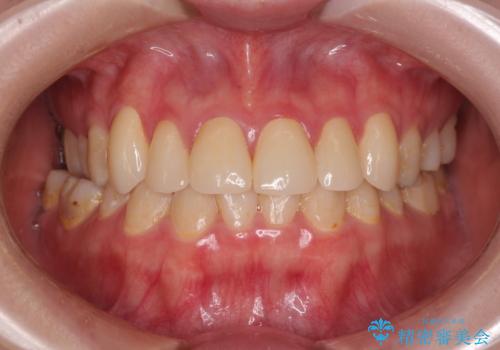

拡大鏡視野下で保険のプラスチック(コンポジットレジン)、虫歯を除去し、オールセラミッククラウンに適した形にしました。

また今回は6本と本数も多かったため個歯トレーを用いて複数本の歯を正確に型どりしています。

被せものが出来上がってから数回形や色の修正がありましたが機能的にも見た目も大変満足していただきました。